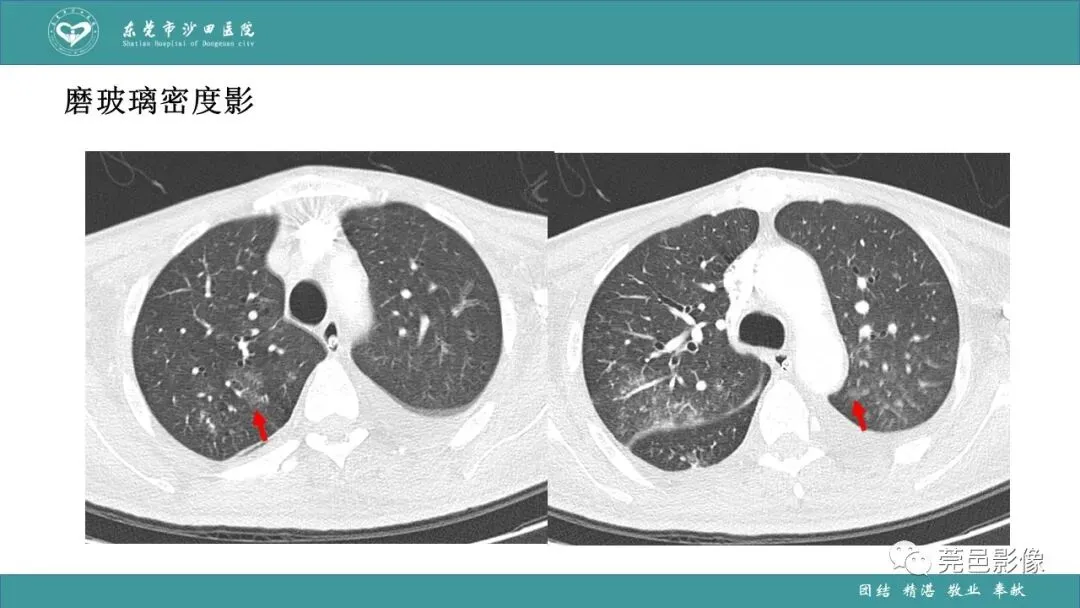

>课件 | 肺炎克雷伯杆菌肺炎影像学诊断与鉴别诊断

课件 | 肺炎克雷伯杆菌肺炎影像学诊断与鉴别诊断